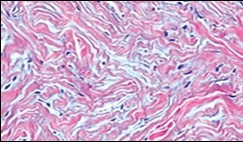

Figure 1.Soft tissue perineurioma with fascicles of bipolar neural cells with elongated cytoplasmic processes, wavy nuclei and an admixture of collagen fibres 11.